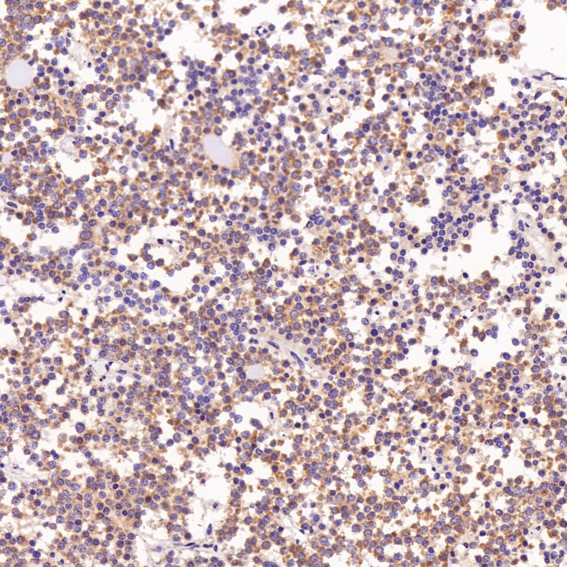

Immunohistochemical analysis of paraffin-embedded Human pituitary tumor, using the Antibody.

Immunohistochemical analysis of paraffin-embedded Human pituitary tumor, using the Antibody.